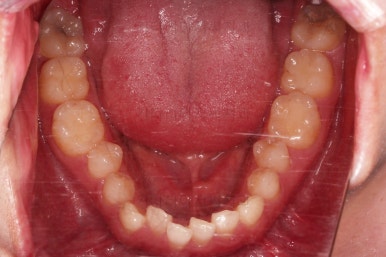

초진 시 입안의 모습입니다.

교합이 많이 안좋습니다.

위아랫니가 서로 엇갈려 가며 지그재그로 껴 들어가야 어금니 맞물림이 생기는데요.

이번 환자분은 아랫니, 아래턱이 전반적으로 앞으로 나와 있어서 교합이 전혀 안되고 있는 상태였습니다.